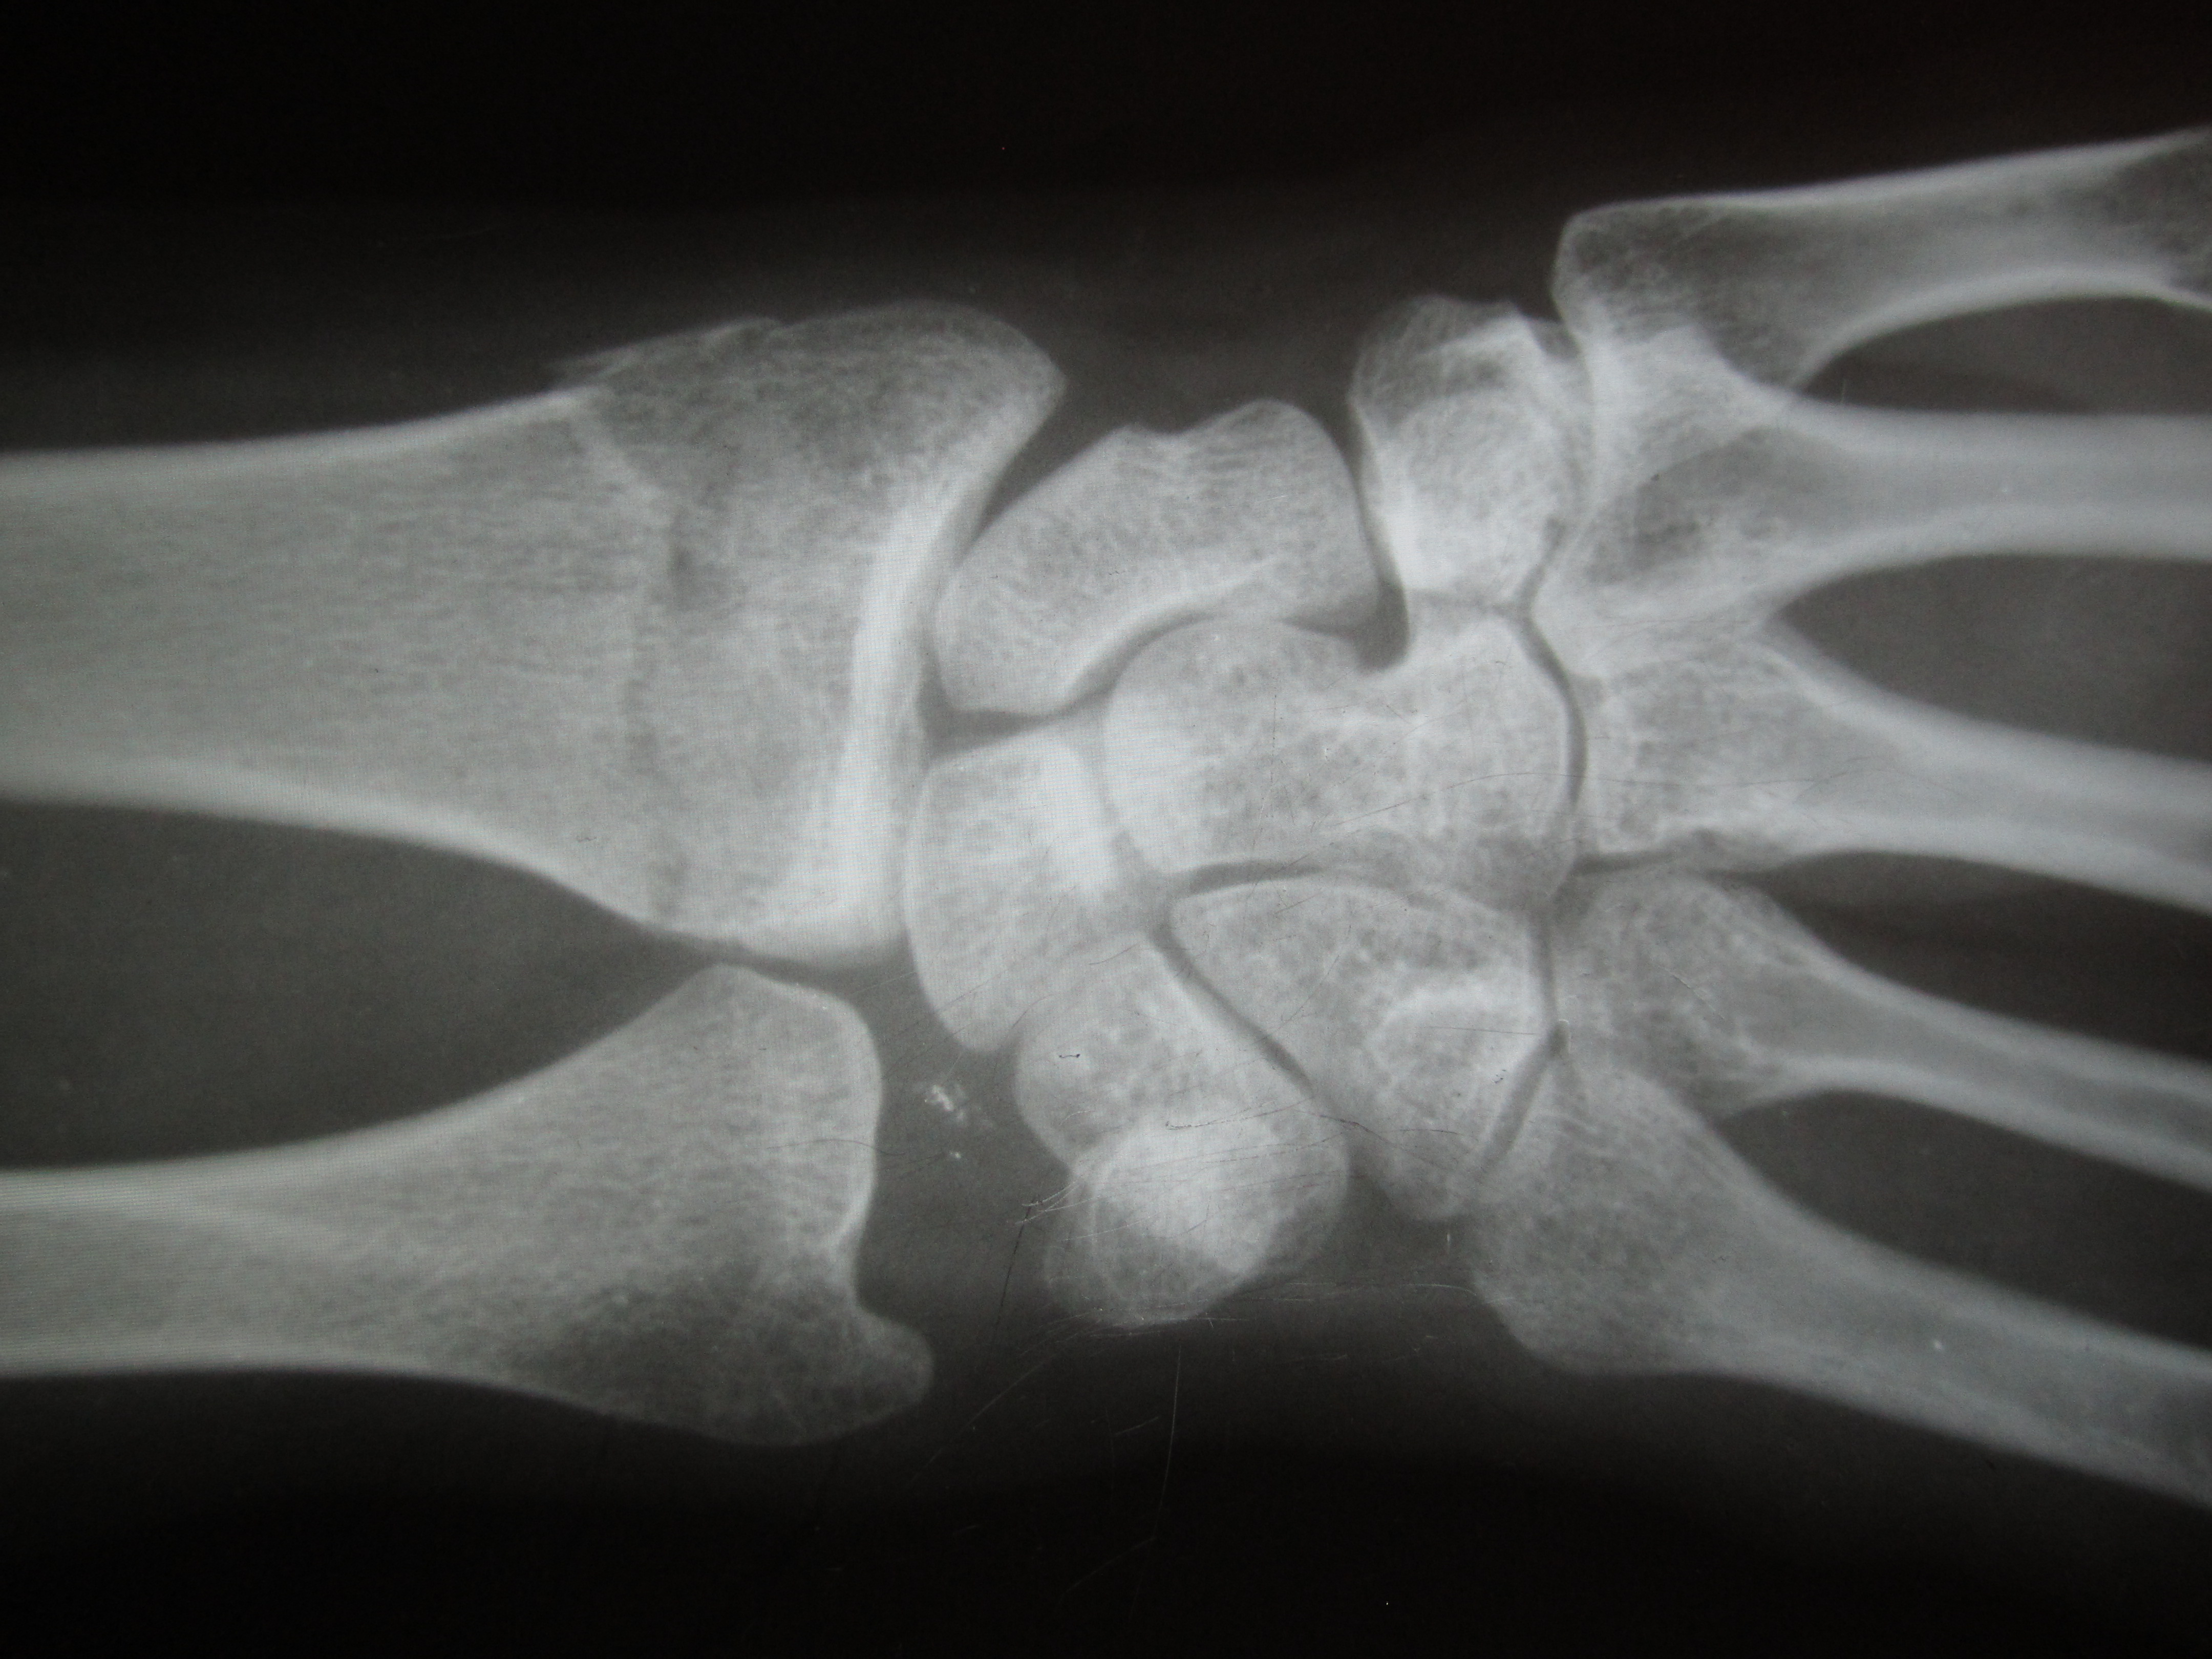

Изображения повреждения костей